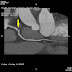

冠動脈CT検査のプロトコールを変更することにしました。 ニトログリセリンとコアベータの使用

| Fig. 1 LAD evaluated with 64-row MDCT |

Fig. 2は、冠動脈造影像です。PCIになるものとばかり考えていましたのでNTG投与下の造影です。#6には50%狭窄しかありません。

| Fig. 2 Left Coronary Artery after NTG IC |

今まで当院での冠動脈CT検査時に、検査前のニトログリセリンは使用していませんでした。多くの病院で使用しているにもかかわらず使用していなかった理由は、折角ベータブロッカーの内服で心拍数が落ちてきたものがNTGの使用でまた心拍数が上がり、冠動脈の評価の質が落ちるのではないかと危惧したからです。こうした心拍数の変化で検査時間が延長することもいやでした。

しかし、今回のような例を見ると冠動脈CT前にNTGの使用は避けて通れないものと思えます。明日以後の冠動脈CT撮影時にはNTG舌下を先行させるプロトコールに変更することにしました。心拍数のコントロールには最近、冠動脈CT用に使用が認められたコアベータを使用するつもりです。この方法で検査をすればいつ効いてくるかわからない内服のベータブロッカーの効果発現を待たなくても済みます。